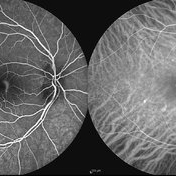

Best Disease Best DiseaseMar 9 2013 by Hamid Ahmadieh, MD FA and ICG Angiography of the left eye of a 49-year-old man with advanced Best disease. Photographer: Soodabeh Fooladin, Negah Eye Center, Tehran Imaging device: Heidelberg Spectralis Condition/keywords: Best disease, indocyanine green (ICG) angiography